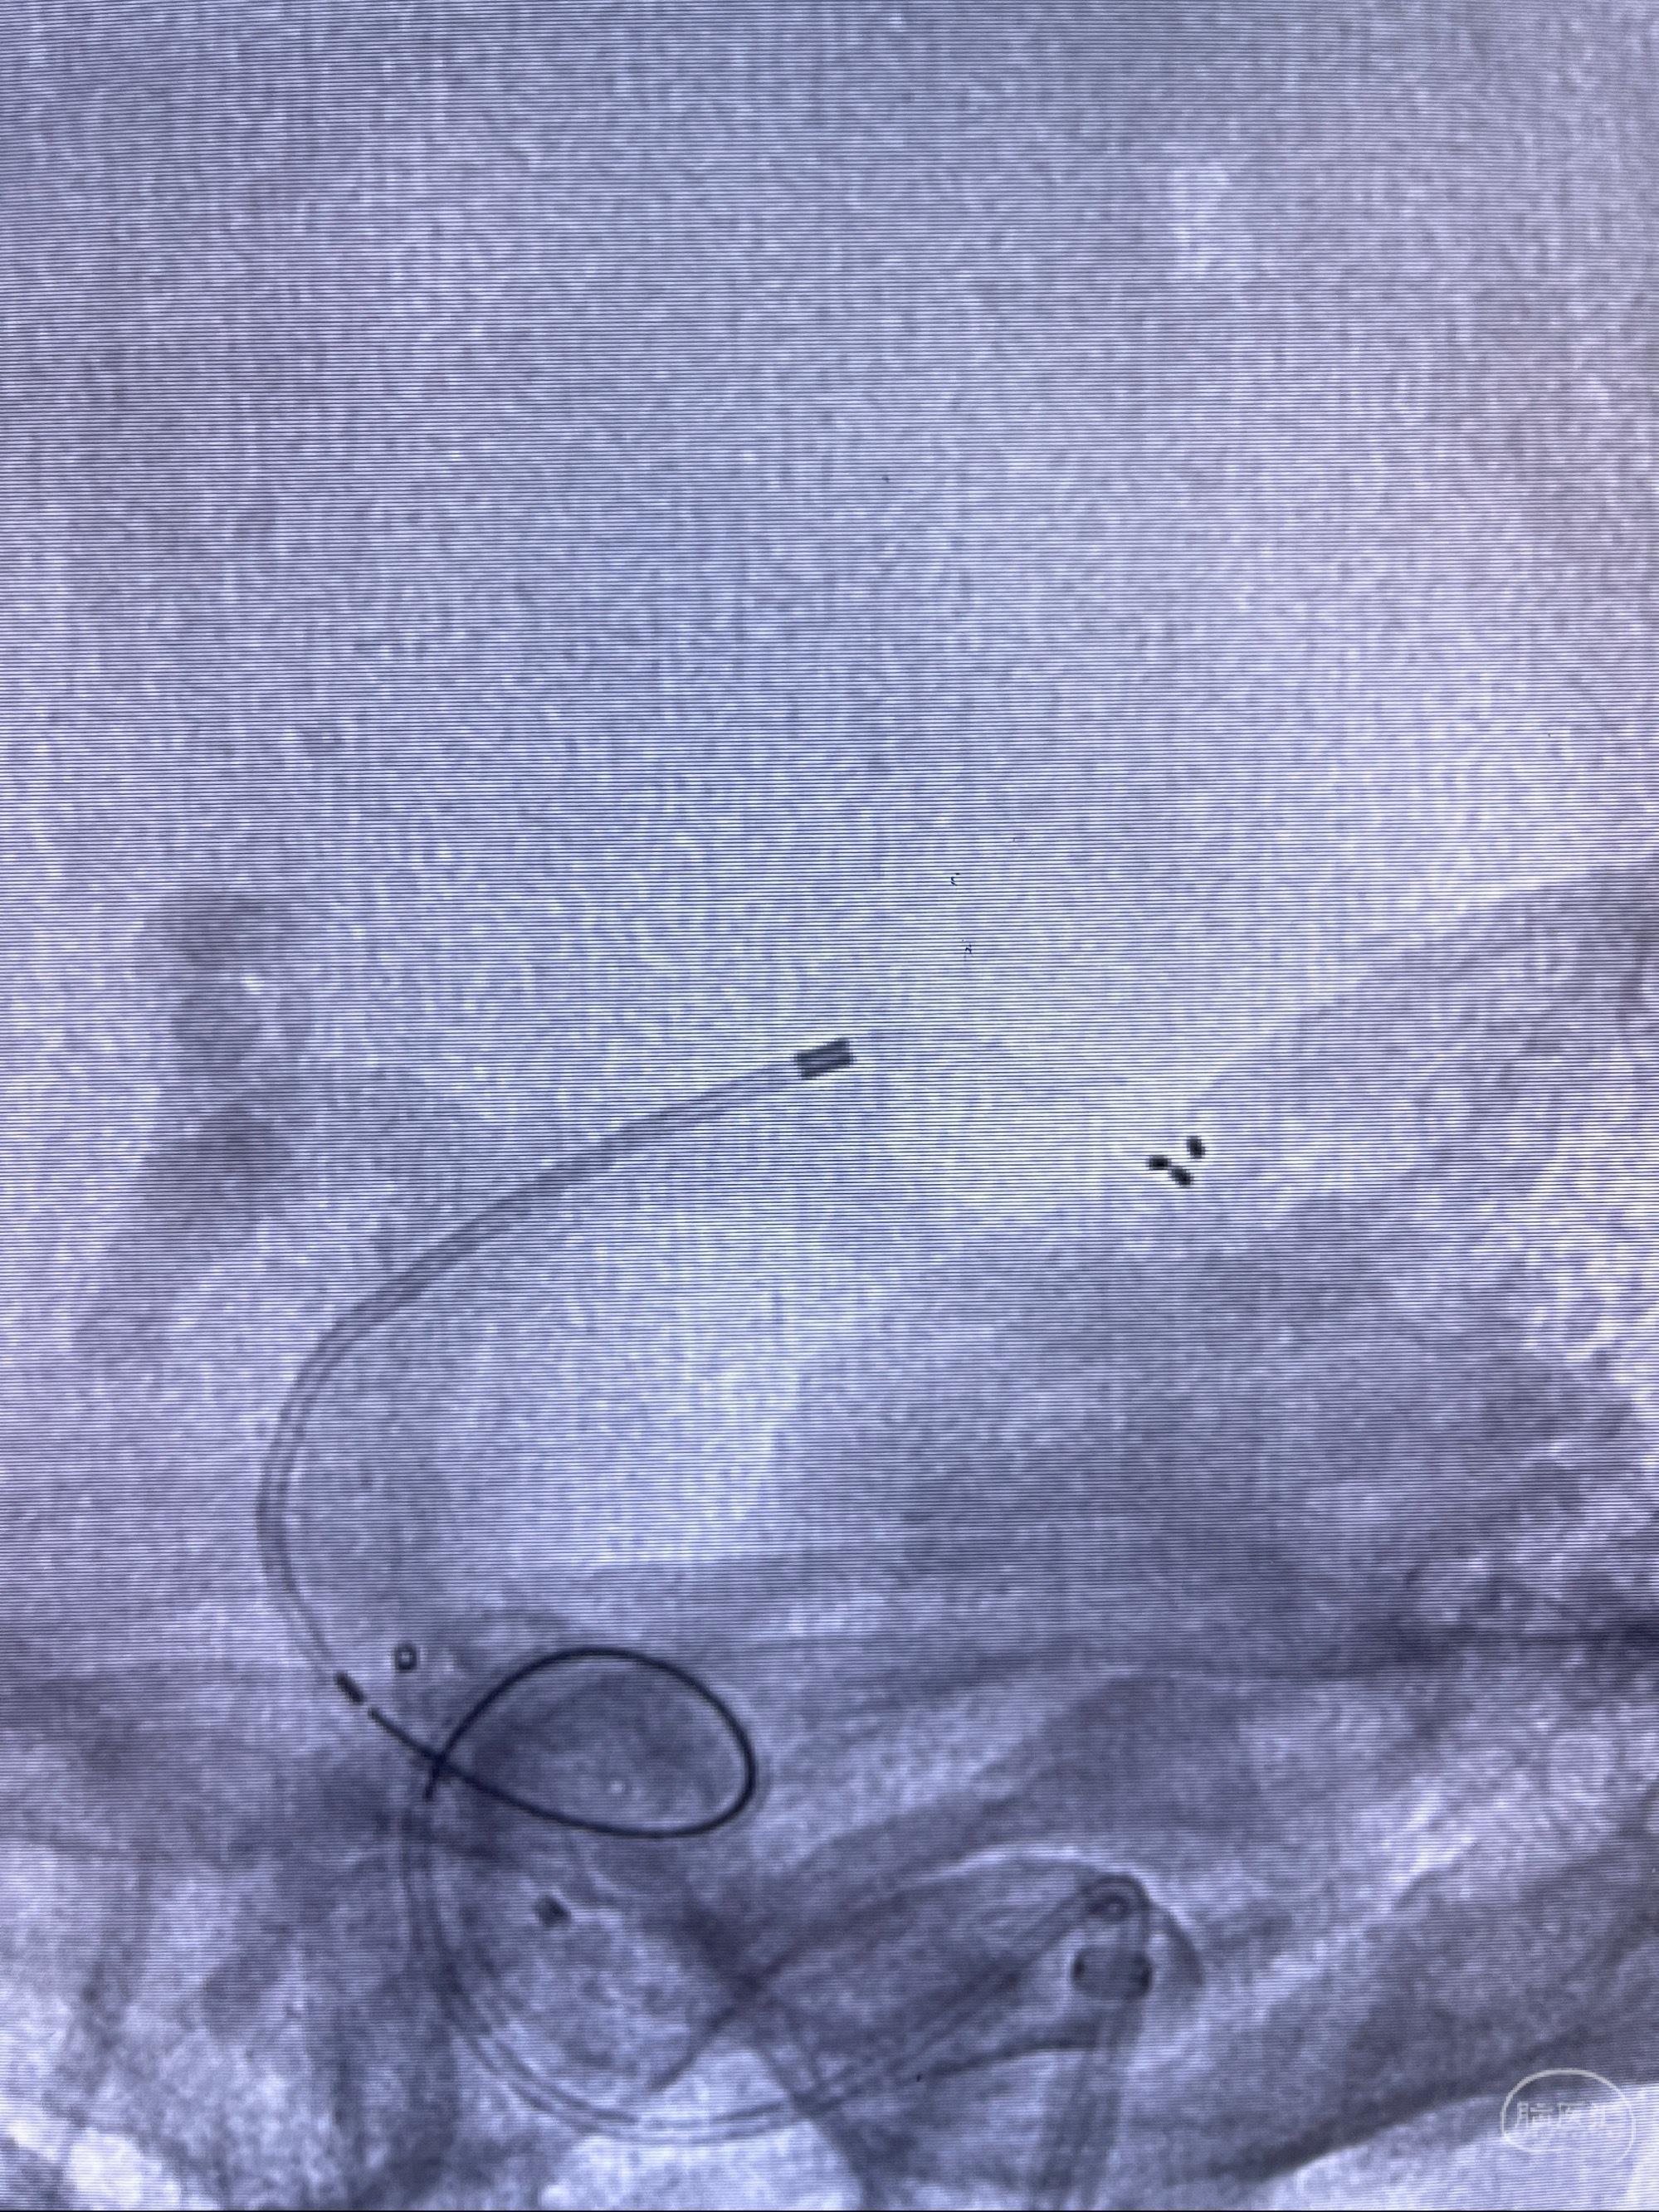

2023-08-14DSA:

左侧大脑中动脉动脉瘤,约2.6-2.8-3.4-2mm大小(瘤颈部、瘤体部、瘤高)

1.左侧大脑中动脉动脉瘤,约2.6-2.8-3.4-2mm大小(瘤颈部、瘤体部、瘤高)

2.外科手术夹闭or介入支架辅助栓塞

麻醉苏醒佳,遵嘱动作

术后即刻CT